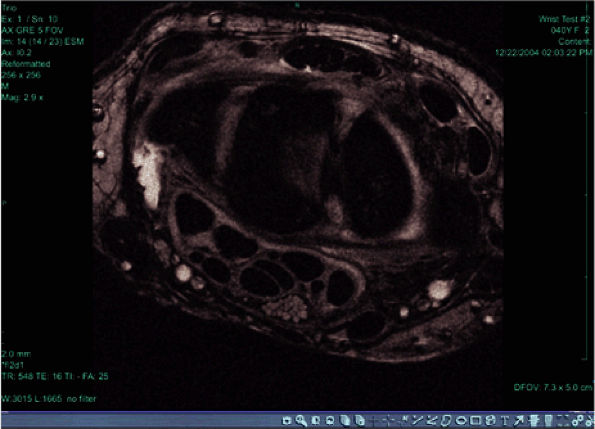

![]() |

|

FIGURE 2.9 ● High-resolution image acquired with a 3T version of the wrist array coil. Note the nerve bundle.